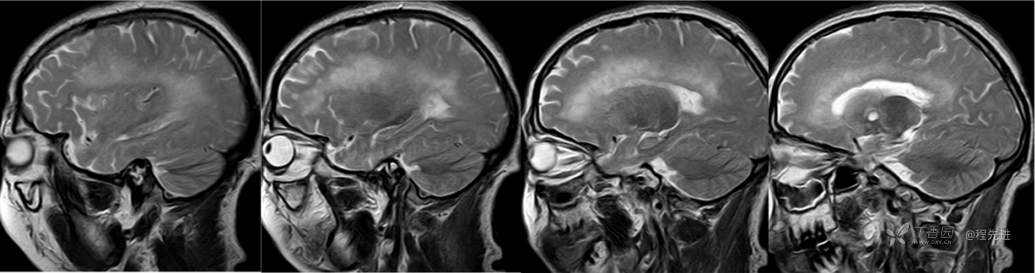

MR

T1

T2矢状位